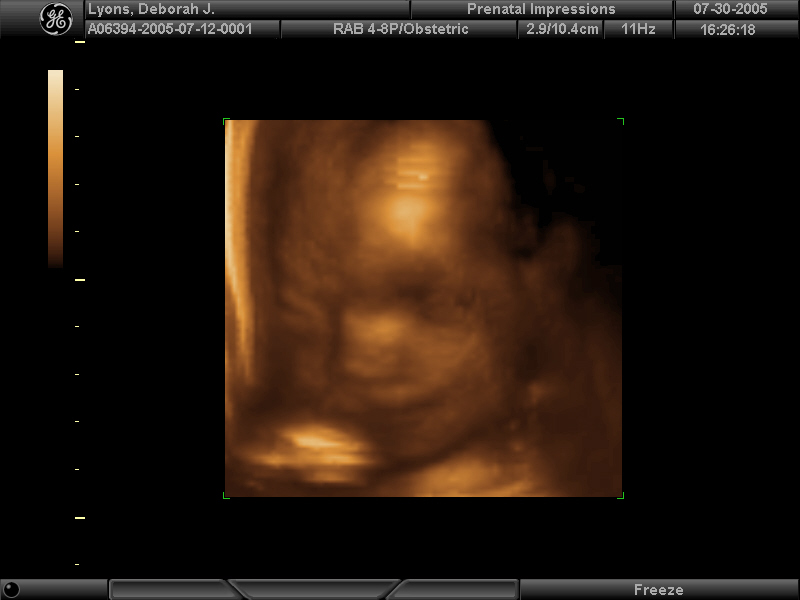

3d -- baby_lyons__23.jpg